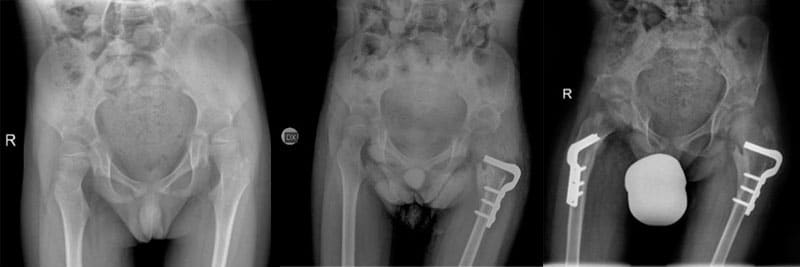

The aim of the work was to evaluate the results of hip reconstruction as a surgical treatment for hip dislocation in children with cerebral palsy.

The technique used is to redirect the bones of the femur and pelvis after cutting them (osteotomy), in order to regain a congruent hip joint with normal shape and function.

Patients underwent preoperative radiographic studies and then after 6 and 12 months, and and each subsequent year.